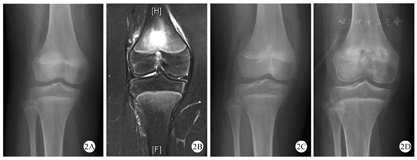

X线是临床上最常用的检查,通常X线在疾病初期无明显改变,随着疾病的进展,X线可显示早期溶骨性病变、硬化、骨扩张或后期呈混合性显像[20,21](图1)。在临床工作中,经验丰富的影像医生才能通过X线检查将CNO与骨肿瘤、感染性骨髓炎鉴别区分。对于无症状的CNO疾病,放射性核素骨显像是常用方法,但因其具有辐射,临床上广泛应用受到限制[22]。MRI是目前最具特异性的影像诊断方法,典型的MRI表现为初期的骨髓水肿,到后期的骨皮质变薄、溶骨性破坏伴硬化(图2、图3、图4)。全身MRI检查在急性炎症期最具有特异性,在MRI可以表现出T1序列低信号和T2序列高信号[21,23]。全身MRI检查在疾病的早期诊断中具有重要的意义,因为它能够在骨溶解、骨硬化之前检测到骨髓水肿和无症状骨病变,并且没有辐射,可用来监测随访骨骼病变的进展演变[24]。(图1、图2、图3、图4中影像学资料均来自同一患者)